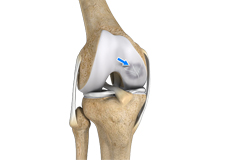

Ligaments are tough bands of tissue that connect one bone to another bone. The ligaments of the knee stabilize the knee joint. There are two important groups of ligaments that hold the bones of the knee joint together, collateral and cruciate ligaments.

Collateral ligaments are present on either side of the knee. They prevent the knee from moving too far during side to side motion. The collateral ligament on the inside is called the medial collateral ligament (MCL) and the collateral ligament on the outside is called the lateral collateral ligament (LCL).

Cruciate ligaments, present inside the knee joint, control the back-and-forth motion of the knee. The cruciate ligament in the front of the knee is called anterior cruciate ligament (ACL) and the cruciate ligament in the back of the knee is called posterior cruciate ligament (PCL).